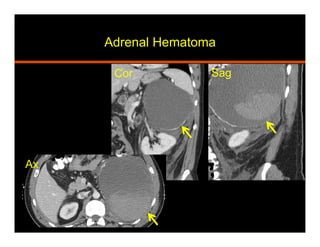

Hemorrhage

•  Traumatic (non accidental in peds) vs non traumatic

•  Non traumatic causes: coagulopathy, stress (sepsis,

surgery, burns, hypotension, pregnancy), venous

hypertension and hemorrhagic tumor

•  20% are bilateral, 1- 5 cm, well defined, round

•  CT: high attenuation (50-90 HU), does not

enhance, decreases in size and attenuation with

time, fat stranding, extension

•  MRI:

Acute (<7 days) – T1 iso to hypo, T2 markedly hypo

Subacute (1-7 wks) – T1 fat sat and T2 hyperintense

Chronic (after 7 wks) – T1 and T2 hypointense rim

Adrenal Hematoma

Sag

Ax

Ax Cor

Cor Sag